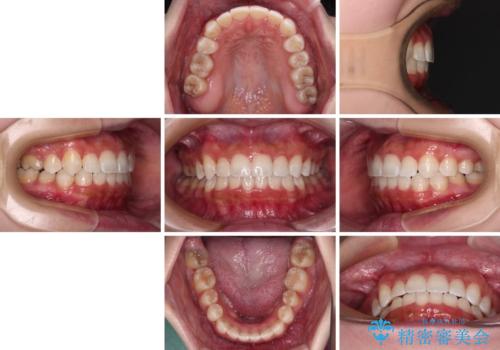

前から5番目の乳歯は、後続永久歯である小臼歯と比べて幅径が大きいため、移動に時間がかかりましたが、きれいに仕上げることができました。